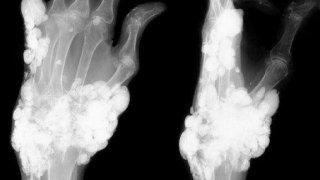

ภาพเดียวซึ้งใจ!!ผัวโพสต์ภาพอาบน้ำ เช็ดถูให้เมีย (เมียท้อง) #เพราะในใจของผม #ไม่มีผู้หญิงคนไหนแทนที่เธอได้💕 ภาพเดียวซึ้งใจ!!ผัวโพสต์ภาพอาบน้ำ เช็ดถูให้เมีย (เมียท้อง) #เพราะในใจของผม #ไม่มีผู้หญิงคนไหนแทนที่เธอได้💕บอร์ด เรื่องน่ารักๆ ซึ้งๆ, โพสท์โดย ลูกสาวอบตห้าปี, 8Yเลือดกระจายเต็มเตียง!! หมอฟันเตือน สาวจัดฟันทำออรัลเซ็กส์แฟนหนุ่ม เหล็กจัดฟันพลาดเกี่ยวของรัก เจ็บเลือดพุ่ง เลือดกระจายเต็มเตียง!! หมอฟันเตือน สาวจัดฟันทำออรัลเซ็กส์แฟนหนุ่ม เหล็กจัดฟันพลาดเกี่ยวของรัก เจ็บเลือดพุ่งบอร์ด ข่าววันนี้, โพสท์โดย ลูกสาวอบตห้าปี, 8Yวิจัยแบบสอบถาม คุณคิดว่าการแต่งตัวโป๊ของผู้หญิง คือการยั่วยวนชาย ใช่หรือไม่ วิจัยแบบสอบถาม คุณคิดว่าการแต่งตัวโป๊ของผู้หญิง คือการยั่วยวนชาย ใช่หรือไม่ บอร์ด ข่าววันนี้, โพสท์โดย มิ้นส์, 8Yคลิประทึก! รถยนต์ชนกลุ่มเด็กแว๊นซ์ที่กำลังจะพากันมาปิดถนน ด้านพ่อแม่ลั่นลูกแค่กำลังจะขี่รถกลับบ้าน คลิประทึก! รถยนต์ชนกลุ่มเด็กแว๊นซ์ที่กำลังจะพากันมาปิดถนน ด้านพ่อแม่ลั่นลูกแค่กำลังจะขี่รถกลับบ้านบอร์ด ข่าววันนี้, โพสท์โดย หนูขายมาลัย, 8Yแอปหาเพื่อนบนโลกออนไลน์ แอปหาเพื่อนบนโลกออนไลน์ บอร์ด ความรัก, ประสบการณ์ชีวิต, โพสท์โดย abcdefool, 8Yหนุ่มเบาใจแฟนสาวไปเที่ยวทะเล ส่งรูปมารายงานตลอด แต่ชาวเน็ตดันไปโฟกัสที่ซองเล็กๆ เป็นเรื่องเลย หนุ่มเบาใจแฟนสาวไปเที่ยวทะเล ส่งรูปมารายงานตลอด แต่ชาวเน็ตดันไปโฟกัสที่ซองเล็กๆ เป็นเรื่องเลยโพสท์โดย หนูขายมาลัย, 8Y  หน้าพังจนแฟนนอนด้วยไม่ลง การบ้านก็ไม่ทำ เซ็งค่ะบอร์ด ถามตอบ พูดคุย, โพสท์โดย yayoijang, 8Y  สะเทืือนใจ ผช.เนียนมาจับหน้าอกในผับ แต่เราไม่รู้ตัวเลย (ฟองน้ำล้วนๆ)บอร์ด ถามตอบ พูดคุย, โพสท์โดย bookmark, 8Y  เห็นผู้ชายช่วยตัวเองในที่สาธารณะ อยากกรี๊ดมากแต่อายค่ะบอร์ด ถามตอบ พูดคุย, โพสท์โดย adult, 8Yออเจ้า ข้าเขินแล้วเจ้าคะ!! รวมฉากจิ้นละคร บุพเพสันนิวาส โป๊ป ปั้นจั่น ส่งสายตาหวานน้ำตาล ยอม!! ออเจ้า ข้าเขินแล้วเจ้าคะ!! รวมฉากจิ้นละคร บุพเพสันนิวาส โป๊ป ปั้นจั่น ส่งสายตาหวานน้ำตาล ยอม!!บอร์ด รวมมิตรซุปเปอร์ตลก, โพสท์โดย funny00, 8Yเล่นแผลงๆ นักดำน้ำหนุ่ม เห็นหอยมือเสืออ้าใต้ทะเล ควักจู๋แหย่โดนหนีบ หามส่งรพ.แทบไม่ทัน เล่นแผลงๆ นักดำน้ำหนุ่ม เห็นหอยมือเสืออ้าใต้ทะเล ควักจู๋แหย่โดนหนีบ หามส่งรพ.แทบไม่ทันโพสท์โดย การะโกด, 8Yมาโวตกัน ผู้ชายน่ากินที่สุดตรงไหน ^^ มาโวตกัน ผู้ชายน่ากินที่สุดตรงไหน ^^ โพสท์โดย สมาชิกหมายเลข 1721187, 8Yความสัมพันธ์ของหูดหงอนไก่กับมะเร็งปากมดลูก ความสัมพันธ์ของหูดหงอนไก่กับมะเร็งปากมดลูกบอร์ด สาระ เกร็ดน่ารู้, โพสท์โดย poptu, 8Yน่าสน!! หวีกระจอ#โปรดอย่าใช้ผิดประเภท น่าสน!! หวีกระจอ#โปรดอย่าใช้ผิดประเภทบอร์ด แปลก แปลก แปลก, โพสท์โดย ลูกสาวอบตห้าปี, 8Yอัยการเลื่อนสั่งคดี "สายป่าน" โพสต์ภาพของลับแฟนหนุ่มลง IG อัยการเลื่อนสั่งคดี "สายป่าน" โพสต์ภาพของลับแฟนหนุ่มลง IGบอร์ด บันเทิง ดารา, โพสท์โดย kaoaottt, 8Yเจ๊ระเบียบหนุนรัฐ ให้มีถุงยางอนามัยในโรงเรียน และทำให้เป็นเรื่องปกติของวัยรุ่น เจ๊ระเบียบหนุนรัฐ ให้มีถุงยางอนามัยในโรงเรียน และทำให้เป็นเรื่องปกติของวัยรุ่นบอร์ด ข่าววันนี้, โพสท์โดย ลูกสาวอบตห้าปี, 8Yวาดรูปการ์ตูนออเจ้า (ทีละขั้นตอน Step By Step) วาดรูปการ์ตูนออเจ้า (ทีละขั้นตอน Step By Step)บอร์ด สาระ เกร็ดน่ารู้, โพสท์โดย Nuy Taluang, 8Yประวัติปืน:DESERT EAGLE MARK XIX ประวัติปืน:DESERT EAGLE MARK XIXบอร์ด มือถือ Gadget เทคโนโลยี, โพสท์โดย มารคัส, 8Yรีวิวเสื้อบอลทีมชาติไทย #ใส่ได้2ด้าน อู้วหูว์ รีวิวเสื้อบอลทีมชาติไทย #ใส่ได้2ด้าน อู้วหูว์บอร์ด การเมืองและข่าวสาร, โพสท์โดย กระบี่ พเนจร, 8Yสาวร้อง! นักฟุตบอลดีกรีระดับทีมชาติ ทำท้องแล้วไม่รับ!? สาวร้อง! นักฟุตบอลดีกรีระดับทีมชาติ ทำท้องแล้วไม่รับ!?โพสท์โดย การะโกด, 8Yหนุ่มปล่อยโฮ จับได้คาหนังคาเขา เมียมีชู้! แถมตั้งท้องให้ดูต่างหน้า สุดท้ายคดีกลับพลิก ชาวเน็ตด่ายับ! หนุ่มปล่อยโฮ จับได้คาหนังคาเขา เมียมีชู้! แถมตั้งท้องให้ดูต่างหน้า สุดท้ายคดีกลับพลิก ชาวเน็ตด่ายับ!บอร์ด ความรัก, ประสบการณ์ชีวิต, โพสท์โดย ลูกสาวอบตห้าปี, 8Y”เลขเด็ดนายก บิ๊กตู่” ลุ้นทะเบียนซ้ำ เลขอายุมาแรง งวดนี้ 1/4/61 ”เลขเด็ดนายก บิ๊กตู่” ลุ้นทะเบียนซ้ำ เลขอายุมาแรง งวดนี้ 1/4/61บอร์ด หวย, โพสท์โดย kukik2534, 8Yบรูโน โบบัน เสียชีวิตในสนามแบบสุดช็อก… (คลิป) บรูโน โบบัน เสียชีวิตในสนามแบบสุดช็อก… (คลิป)บอร์ด ข่าวกีฬา, โพสท์โดย kukik2534, 8Yโหดไร้ปราณี ลวงหัวหน้าวินแท็กซี่ ปาดคอชิงทรัพย์ หรือล้างหนี้ โหดไร้ปราณี ลวงหัวหน้าวินแท็กซี่ ปาดคอชิงทรัพย์ หรือล้างหนี้โพสท์โดย การะโกด, 8Yนักเรียนหญิง ป.5 ถูกพวกสวะสังคมข่มขืนจนตั้งท้อง อยากเล่าระบาย สิ่งที่ตนเองต้องเจอและกำลังเป็นอยู่ นักเรียนหญิง ป.5 ถูกพวกสวะสังคมข่มขืนจนตั้งท้อง อยากเล่าระบาย สิ่งที่ตนเองต้องเจอและกำลังเป็นอยู่บอร์ด ความรัก, ประสบการณ์ชีวิต, โพสท์โดย หนูขายมาลัย, 8Yสะเทือนใจ! กู้ภัยช่วยกระบะพลิกคว่ำ ผงะ! พบผู้ตายกลายเป็นศพพ่อตัวเอง ร่ำไห้เข่าทรุดลงกับพื้น สะเทือนใจ! กู้ภัยช่วยกระบะพลิกคว่ำ ผงะ! พบผู้ตายกลายเป็นศพพ่อตัวเอง ร่ำไห้เข่าทรุดลงกับพื้นโพสท์โดย More Shit station, 8Yสาวอึ้ง!! ถูกสวมชื่อสั่งซื้อของจากเว็บดัง ได้กระป๋องแปลกๆ เหมือนถูกคุกคามจากคนโรคจิต สาวอึ้ง!! ถูกสวมชื่อสั่งซื้อของจากเว็บดัง ได้กระป๋องแปลกๆ เหมือนถูกคุกคามจากคนโรคจิตบอร์ด ข่าววันนี้, โพสท์โดย ลูกสาวอบตห้าปี, 8Yชอบเที่ยวอาบอบนวดเป็นเหตุ ‘ดม ชวนชื่น’ ปฏิเสธรับศิลปินแห่งชาติ กลัวทำเสื่อมเสีย ชอบเที่ยวอาบอบนวดเป็นเหตุ ‘ดม ชวนชื่น’ ปฏิเสธรับศิลปินแห่งชาติ กลัวทำเสื่อมเสียบอร์ด บันเทิง ดารา, โพสท์โดย ลูกสาวอบตห้าปี, 8Yเชื่อใคร??!! สีกาอ้างเจ้าอาวาสเสพเมถุนจนท้อง-บังคับทำแท้ง ด้านพระแจงไม่ให้เงินกินเหล้า เลยสร้างเรื่องมาใส่ร้าย เชื่อใคร??!! สีกาอ้างเจ้าอาวาสเสพเมถุนจนท้อง-บังคับทำแท้ง ด้านพระแจงไม่ให้เงินกินเหล้า เลยสร้างเรื่องมาใส่ร้ายบอร์ด ข่าววันนี้, โพสท์โดย ลูกสาวอบตห้าปี, 8Yช็อกทั้งเวที !!! นาทีจระเข้งับหัวครูฝึก ช็อกทั้งเวที !!! นาทีจระเข้งับหัวครูฝึกบอร์ด การเมืองและข่าวสาร, โพสท์โดย กระบี่ พเนจร, 8Yสีมงคลประจำวัน เลือกให้ถูกโฉลก ดวงวันเกิด เสริมโชคลาภ เพิ่มเสน่ห์ สีมงคลประจำวัน เลือกให้ถูกโฉลก ดวงวันเกิด เสริมโชคลาภ เพิ่มเสน่ห์บอร์ด ดูดวง เรื่องลึกลับ, โพสท์โดย kukik2534, 8Yหน้าปฐม-นมมหา'ลัย!! อึ๋มทะยานฟ้า ต้องเธอคนนี้ “น้องภา” ทะเลร้อนฉ่ากับ บิกินนี่จิ๋วรัดติ๋ว หน้าปฐม-นมมหา'ลัย!! อึ๋มทะยานฟ้า ต้องเธอคนนี้ “น้องภา” ทะเลร้อนฉ่ากับ บิกินนี่จิ๋วรัดติ๋วบอร์ด เรื่องน่ารักๆ ซึ้งๆ, โพสท์โดย ลูกสาวอบตห้าปี, 8Yจับตาดู เบลล่าขึ้นแท่นเบอร์หนึ่ง จากแม่การะเกด สู่ โสเภณี ในกรงกรรม จับตาดู เบลล่าขึ้นแท่นเบอร์หนึ่ง จากแม่การะเกด สู่ โสเภณี ในกรงกรรมบอร์ด บันเทิง ดารา, โพสท์โดย ลูกสาวอบตห้าปี, 8Y"วันนี้หนูไม่ได้เป็นรองใครอีกต่อไป"ตะวัน ปภัฑนัญ สาวไทยตัวเต็งเวทีนางแบบโลก Miss supermodel worldwide 2018. "วันนี้หนูไม่ได้เป็นรองใครอีกต่อไป"ตะวัน ปภัฑนัญ สาวไทยตัวเต็งเวทีนางแบบโลก Miss supermodel worldwide 2018.โพสท์โดย goldenlotus, 8Yพััฒนาการการตั้งครรภ์ อาการคนท้องที่ผู้หญิงควรรู้ พััฒนาการการตั้งครรภ์ อาการคนท้องที่ผู้หญิงควรรู้บอร์ด ประชาสัมพันธ์ข่าวสาร, โพสท์โดย Pattricia, 8Yซวยแล้ว!! ฟ้องหย่าเพราะจิ๋มเหม็นเป็นข่าวปลอม แชร์ฎีกาผิดอ้างหญิงเหม็นฟ้องหย่าผิดพ.ร.บ.คอมฯ ซวยแล้ว!! ฟ้องหย่าเพราะจิ๋มเหม็นเป็นข่าวปลอม แชร์ฎีกาผิดอ้างหญิงเหม็นฟ้องหย่าผิดพ.ร.บ.คอมฯบอร์ด ข่าววันนี้, โพสท์โดย ลูกสาวอบตห้าปี, 8Yรวบคนขับแท็กซี่ อุ้มนักร้องสาวเข้าโรงแรมได้แล้ว อ้างเห็นเมาหลับ จึงเปิดห้องให้พักผ่อน! รวบคนขับแท็กซี่ อุ้มนักร้องสาวเข้าโรงแรมได้แล้ว อ้างเห็นเมาหลับ จึงเปิดห้องให้พักผ่อน!บอร์ด ข่าววันนี้, โพสท์โดย namech, 8Yซินดี้ โพสท์ระบาย กรณี จนท.ให้ผู้หญิงงดแต่ง sexy กันถูกลวนลามในวันสงกรานต์ ชี้ไม่ใช่ความผิดของผู้หญิง! ซินดี้ โพสท์ระบาย กรณี จนท.ให้ผู้หญิงงดแต่ง sexy กันถูกลวนลามในวันสงกรานต์ ชี้ไม่ใช่ความผิดของผู้หญิง!โพสท์โดย More Shit station, 8Yภาพน่าขนลุกของร่างกายมนุษย์ ที่หลายคนอาจไม่เคยเห็นมาก่อน (แม้จะสยอง แต่สาระล้วนๆ) ตอนที่ 2 ภาพน่าขนลุกของร่างกายมนุษย์ ที่หลายคนอาจไม่เคยเห็นมาก่อน (แม้จะสยอง แต่สาระล้วนๆ) ตอนที่ 2โพสท์โดย More Shit station, 8Yภาพน่าขนลุกของร่างกายมนุษย์ ที่หลายคนอาจไม่เคยเห็นมาก่อน (แม้จะสยอง แต่สาระล้วนๆ) ตอนที่ 1 ภาพน่าขนลุกของร่างกายมนุษย์ ที่หลายคนอาจไม่เคยเห็นมาก่อน (แม้จะสยอง แต่สาระล้วนๆ) ตอนที่ 1โพสท์โดย More Shit station, 8Y